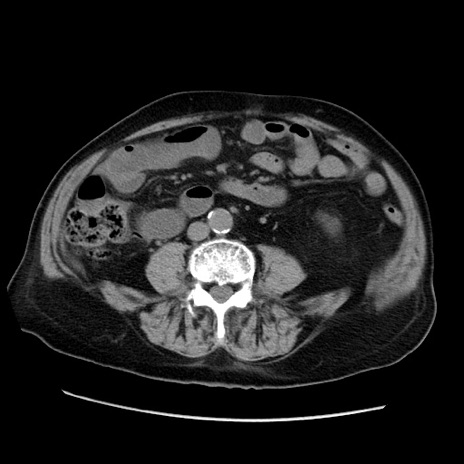

冠状断像

【症例】70歳代男性

【主訴】腹痛

【現病歴】肝硬変・肝細胞癌にてかかりつけの方。約9時間前に食後より腹痛出現。症状が徐々に増悪し、嘔吐出現したため来院。

【既往歴】肝硬変、肝細胞癌(RFA、TACE後)

【身体所見】意識清明、表情苦悶様、BT 36℃、BP 129/78mmHg、P 88bpm、SpO2 97%(RA)、右上腹部から心窩部にかけて圧痛あり、反跳痛なし、筋性防御あり。

【データ】WBC 5800、CRP 0.16